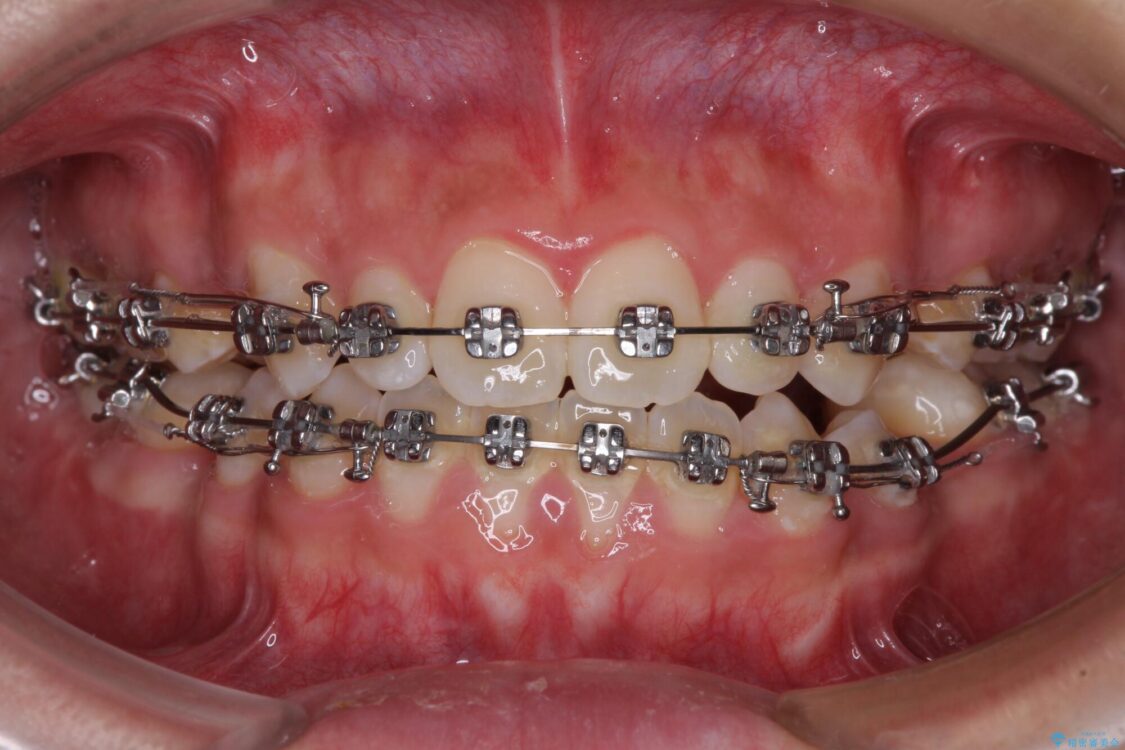

治療途中

• 口元の突出感を改善 受け口傾向の咬み合わせの抜歯矯正 治療途中画像

奥歯の咬み合わせを改善させた後、上下左右の小臼歯(下顎は残存乳歯)を計4本抜歯し、ワイヤー装置にて口元の突出感を改善しながら咬み合わせを整えることとしました。

下顎の残存乳歯は小臼歯よりも大きいため、スペースを閉じるために長い期間を必要としますが、予想通りに長期間を要することとなりました。

受け口傾向の方の抜歯矯正は、下顎前歯が舌側に倒れることで歯肉退縮を起こしやすいことが知られていますが、ワイヤーに工夫をすることでリスクを軽減させています。